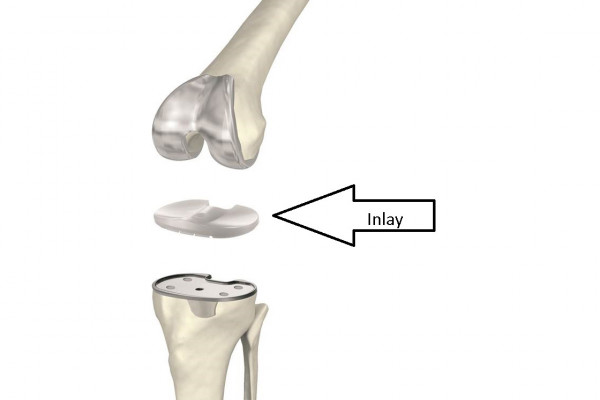

Wechsel des Inlays (Kunststoffeinlage)

Sollte sich im Laufe der Zeit das Inlay abnutzen und eine gewisse Instabilität entstehen, wird der Wechsel des Inlays empfohlen. Vorrausetzung hierfür ist das die übrigen Anteile des Implantates intakt und nicht gelockert sind.